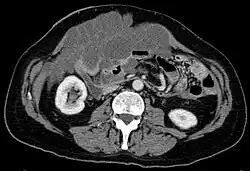

Pseudomyxoma peritonei in der Computertomographie: ausgedehnte hypodense Massen zwischen den Darmschlingen

Im Ultraschallbild (Sonografie) zeigt sich eine echofreie, intraperitoneale, schleimige Masse in der gesamten Bauchhöhle und zwischen den Darmschlingen, in die charakteristische, zarte, streifige Reflexe eingelagert sind. Die Gallerte ist beweglich und verformbar, reagiert aber träger als ein klassischer Aszites. Aufgrund der Zähflüssigkeit zeigen sich groteske, tumorartige Formen.[4] Eine Computertomographie zeigt die Ausdehnung des Pseudomyxoms. In Abhängigkeit von der Ausdehnung sind eventuell zusätzlich endoskopische Untersuchungen von Magen oder Dickdarm, wie Darm- und Magenspiegelung, urologische Untersuchungen oder auch Untersuchungen von Herz und Lunge sowie Blutentnahmen nötig.[2] Als entscheidendes diagnostisches Merkmal gilt die extrazelluläre Schleimproduktion in der Bauchhöhle.[1]